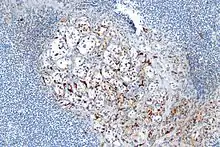

- About 40% of carcinoids have a scattering of sustentacular cells, which stain positive for S-100.[6]